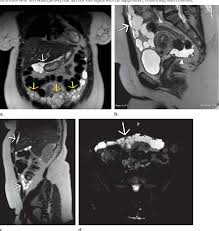

It usually impacts young women. Multicystic peritoneal mesothelioma (mcpm) is a rare cystic proliferation most often seen in women of reproductive age with a history of prior abdominal surgery. From the walls of various sized cysts. Crohn's disease is an inflammatory bowel disease that causes pain and inflammation in any part of the gastrointestinal (gi) tract. A case of cystic peritoneal mesothelioma with repeated local recurrences is presented. Unlike malignant mesothelioma, bmpm has not been shown to have an association with. cystic conditions such as lymphangioma can also enter the. 34possiblygreaterthan that of peritoneal cystic lymphangioma which it resembles grossly andwith whichit maybeconfused Fewer than 200 cases have been reported worldwide. Benign cystic peritoneal mesothelioma is a rare tumor which frequently occurs in women of reproductive age. The patient underwent diagnostic laparoscopy with resection of the mass. In some instances, though, cystic mesothelioma will require some. Diagnosed with cystic peritoneal mesothelioma, she said:

Benign cystic mesothelioma (bcm) is a rare and benign disease that arises from the peritoneal mesothelium. Diagnosed with cystic peritoneal mesothelioma, she said: The histological differential diagnosis of these neoplasms can include reactive mesothelial proliferations, malignant mesothelioma, and metastatic carcinoma. The term mesenteric cyst is often used to refer to cysts that do not connect to the retroperitoneum. 20 benign multicystic peritoneal mesothelioma (bmpm) is a very rare benign cystic tumor arising from the peritoneal mesothelium (lining of the abdominal wall).

Due to the rarity of this tumor, similarity of patient presentation, and comparable features on imaging, the diagnosis of this pathology is. It tends to have a local recurrence. The differential diagnosis of cystic peritoneal masses is broad. Hafner m, novacek g, herbst f, ullrich r, gangl a. Benign multicystic peritoneal mesothelioma is a very rare benign cystic tumor. The benign cystic mesothelioma of the peritoneum is a rare lesion and is known for local recurrence. It may be misdiagnosed as bronchitis, pneumonia, emphysema, asthma, chronic pulmonary obstructive disorder, or a type of lung cancer. In some instances, though, cystic mesothelioma will require some.

It is a rare disease that occurs most often in women of reproductive age and is associated with a history of prior abdominal surgery, endometriosis or inflammatory pelvic disease 6. Whereas malignant mesothelioma can be epithelioid or spindled and exhibits malignant behavior, multicystic peritoneal mesothelioma is a cystic tumor that may be multifocal and has benign behavior. Since cystic mesothelioma is a benign form of mesothelioma, normal life expectancy occurs. Abdominal pain associated with pelvic or abdominal mass is the common clinical presentation. Multicystic peritoneal mesothelioma (mcpm) is a rare cystic proliferation most often seen in women of reproductive age with a history of prior abdominal surgery. peritoneal mesothelioma is a form of cancer caused by asbestos. Benign multicystic peritoneal mesothelioma (bmpm) is a rare neoplasm of the abdominal mesothelium (i.e., peritoneum, mesentery, and omentum). Bbc newsreader kate williams has revealed she has a rare form of cancer. All of the resembled abdominal cystic hygroma (lymphcysts were lined by cells which, while varying angioma. This is first case report of a rapidly developing massive abdominal tumor with histological finding of benign cystic mesothelioma (bcm). peritoneal mesothelial cysts pmc are a clinical dilemma because of their true pathogenic nature. Cavallero a, beretta m and lo menzo e et al (2011) cystic peritoneal mesothelioma: Williams, who works for bbc radio 5 live, said she was diagnosed with cystic peritoneal mesothelioma in 2017.